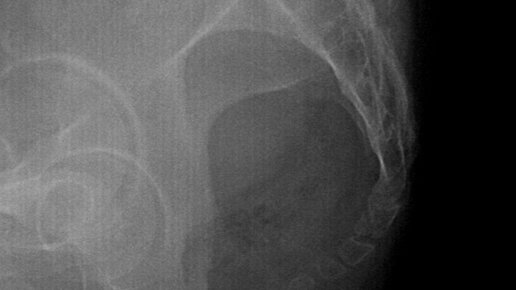

Что такое рентгенография копчика? Это стандартный 2-х мерный рентгеновский снимок, проводимый в двух проекциях(прямой и боковой). Исследование полностью безболезненно и проводится лежа на спине и на боку. Что можно увидеть на снимке? Исследование позволяет рассмотреть состояние нижней части позвоночника, выявить наличие травматических изменений, подобрать лечение. Рентген помогает выявить такие проблемы и заболевания, как: Что может быть показанием к проведению рентгенографии? Боль...

Рентгенографический метод, показывающий поясничный отдел позвоночника, – это простой и доступный метод рентгена. Если говорить о рентгене, то этот вид диагностирования патологий является информативным в плане выявления опухолей, воспалений, переломов, также с помощью него можно выявить дегенеративное заболевание позвоночника. Рентген распространен благодаря доступности, поэтому его можно сделать во всех медицинских учреждениях. В случае, когда невозможно получить необходимые данные, пациенту назначают прохождение МРТ, так как он позволяет визуализировать все органы и ткани...